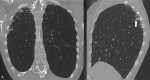

Pleuroparenchymal fibroelastosis in patients affected by systemic sclerosis: What should the rheumatologist do?

Pleuroparenchymal fibroelastosis (PPFE) is a rare new interstitial lung disease (ILD) characterized by the fibrotic thickening of the visceral pleura and subadjacent parenchymal areas of the upper lobes This study reveals that patients with ILD-SSc associated with chest HRCT evidence of PPFE require close and recurrent follow-up with periodic evaluation of lung function parameters, DLCO and chest HRCT. Rheumatologists should be aware of this new radiological finding which is accompanied by a negative prognosis, especially when associated with a progressive course. Patients with this radiological pattern need to be monitored with particular attention.